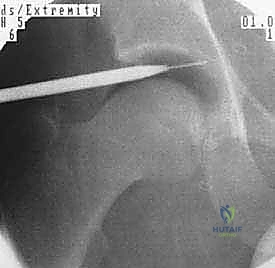

1. التخدير ووضعية المريض

يتم غالباً استخدام التخدير العام أو النصفي. يوضع المريض على طاولة عمليات خاصة تُسمى (Traction Table). يتم سحب الساق برفق شديد لفتح مسافة صغيرة جداً في مفصل الورك (حوالي 1 سم) تسمح بإدخال الكاميرا والأدوات الجراحية بأمان دون إتلاف الغضروف.

2. إحداث الشقوق وإدخال الكاميرا

يتم عمل شقين أو ثلاثة شقوق صغيرة. يُضخ سائل معقم داخل المفصل لتوسيعه وغسل أي بقايا، ثم يتم إدخال كاميرا الألياف الضوئية (Arthroscopy) التي تنقل صورة مكبرة وعالية الدقة (4K) إلى شاشات العرض.